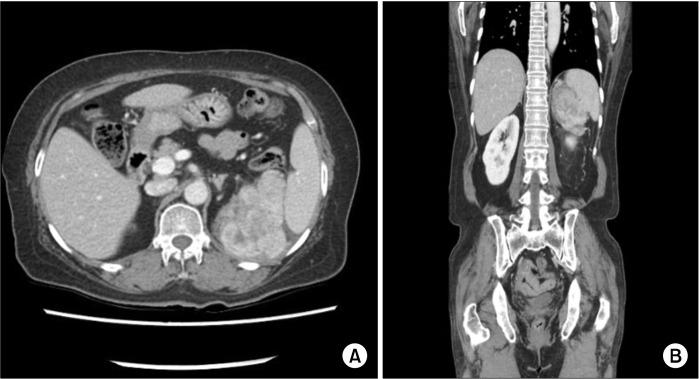

Inflammatory myofibroblastic tumors (IMTs) are a rare chronic inflammatory disease with unclear pathogenesis and pathological features that are not those of a malignant tumor. It is difficult to differentially diagnose them without surgical excision because of their unpredictable clinical behavior, which ranges from benign to locally invasive aggressiveness. We report two cases of IMTs that were diagnosed after surgery. In one case, the IMT originated in peri-splenic area in a 63-year-old female patient. The other case involved a 48-year-old female patient who suffered from an IMT of the head of the pancreas. Both of these cases did not require further treatment based on histological findings, and there has been no evidence of recurrence or metastasis so far. These cases show that the primary choice for the exact diagnosis and proper treatment of IMTs is complete surgical resection.

炎性肌纤维母细胞瘤(IMTs)是一种罕见的慢性炎症性疾病,其发病机制尚不清楚,病理特征也不符合恶性肿瘤的特征。由于其临床行为不可预测,从良性到局部侵袭性,在未进行手术切除的情况下很难进行鉴别诊断。我们报告两例术后诊断为炎性肌纤维母细胞瘤的病例。其中一例,炎性肌纤维母细胞瘤起源于一名63岁女性患者的脾周区域。另一例涉及一名48岁女性患者,她患有胰腺头部的炎性肌纤维母细胞瘤。根据组织学检查结果,这两例均无需进一步治疗,迄今为止也没有复发或转移的证据。这些病例表明,炎性肌纤维母细胞瘤准确诊断和恰当治疗的首要选择是完整的手术切除。